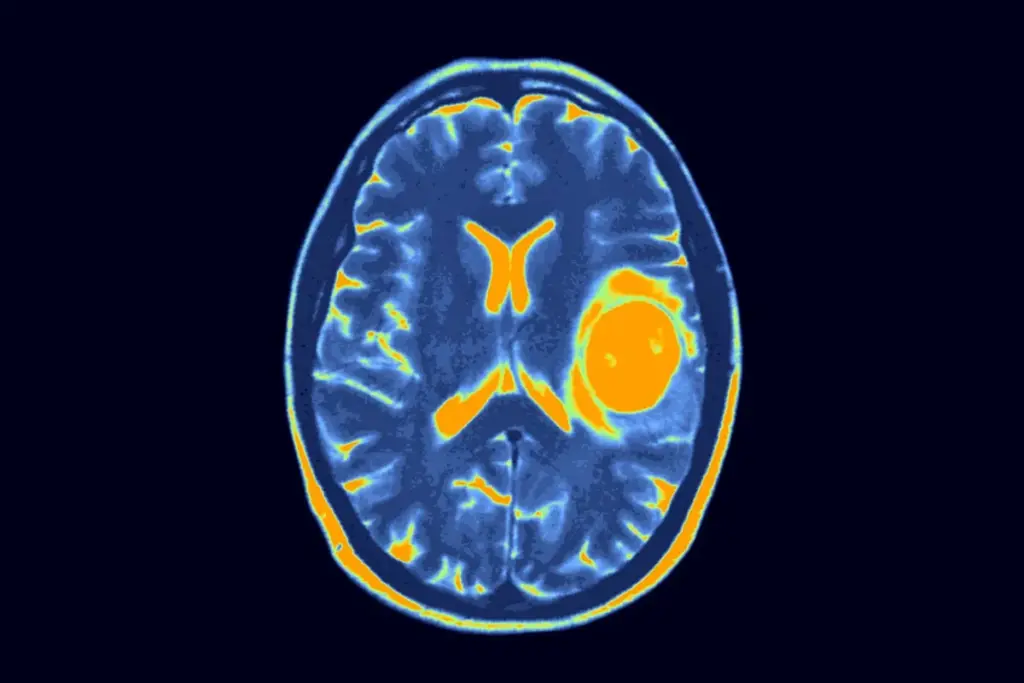

Accurate detection requires highly sophisticated imaging technology and deep neurological expertise. When a patient presents with suspicious cognitive or physical changes specialists immediately order advanced radiological scans to map the cranial cavity.

These scans provide highly detailed three dimensional images revealing the exact location, size and density of the mass. This detailed imaging is absolutely critical for surgical planning and determining whether the growth is pressing against vital functional areas.